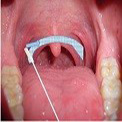

- Führen Sie den Tupfer in die Mundhöhle bis zum Zielgebiet ein. Der Tupfer sollte dabei nicht mit der Zunge, den Zähnen oder der vorderen Mundschleimhaut in Berührung kommen.

Streichen sie unter leichten Drehbewegungen des Tupfers halbkreisförmig über das im Bild markierte Areal. Bild 3 - Führen Sie nun den Tupfer ca. 2 cm tief in die Nase ein und nehmen Sie durch 3 Drehungen an der Naseninnenwand etwas Nasensekret ab. Bild 4

Bild 3